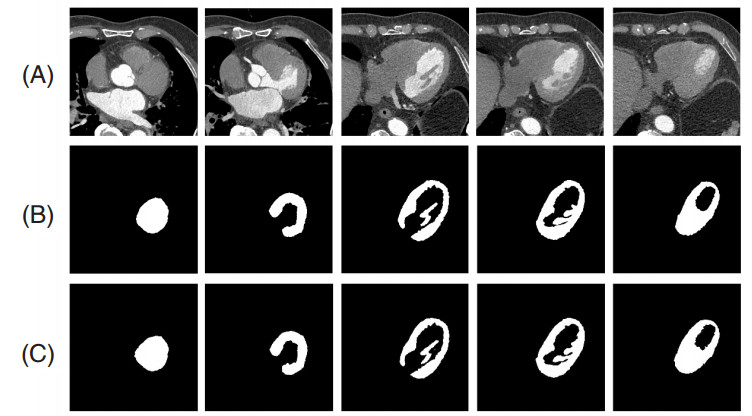

图 3展示了一例患者的5幅CT左心室图像及其相应的分割结果,表 1给出了本文方法分割CT左心室的评估结果。可以看出,本文方法对于CT左心室具有较高的分割精度。其中,Dice=95.20%、IoU=92.12%表明分割得到的左心室区域和标准的左心室区域的空间重合度较高,精确度为97.45%表明分割得到的左心室区域中标准区域占的比重较高,敏感度为94.45%表明分割左心室区域的能力较强。

(A):原图;(B):金标准;(C):本文方法的分割结果 图 3 一例患者的5幅左心室图像及其相应的分割结果